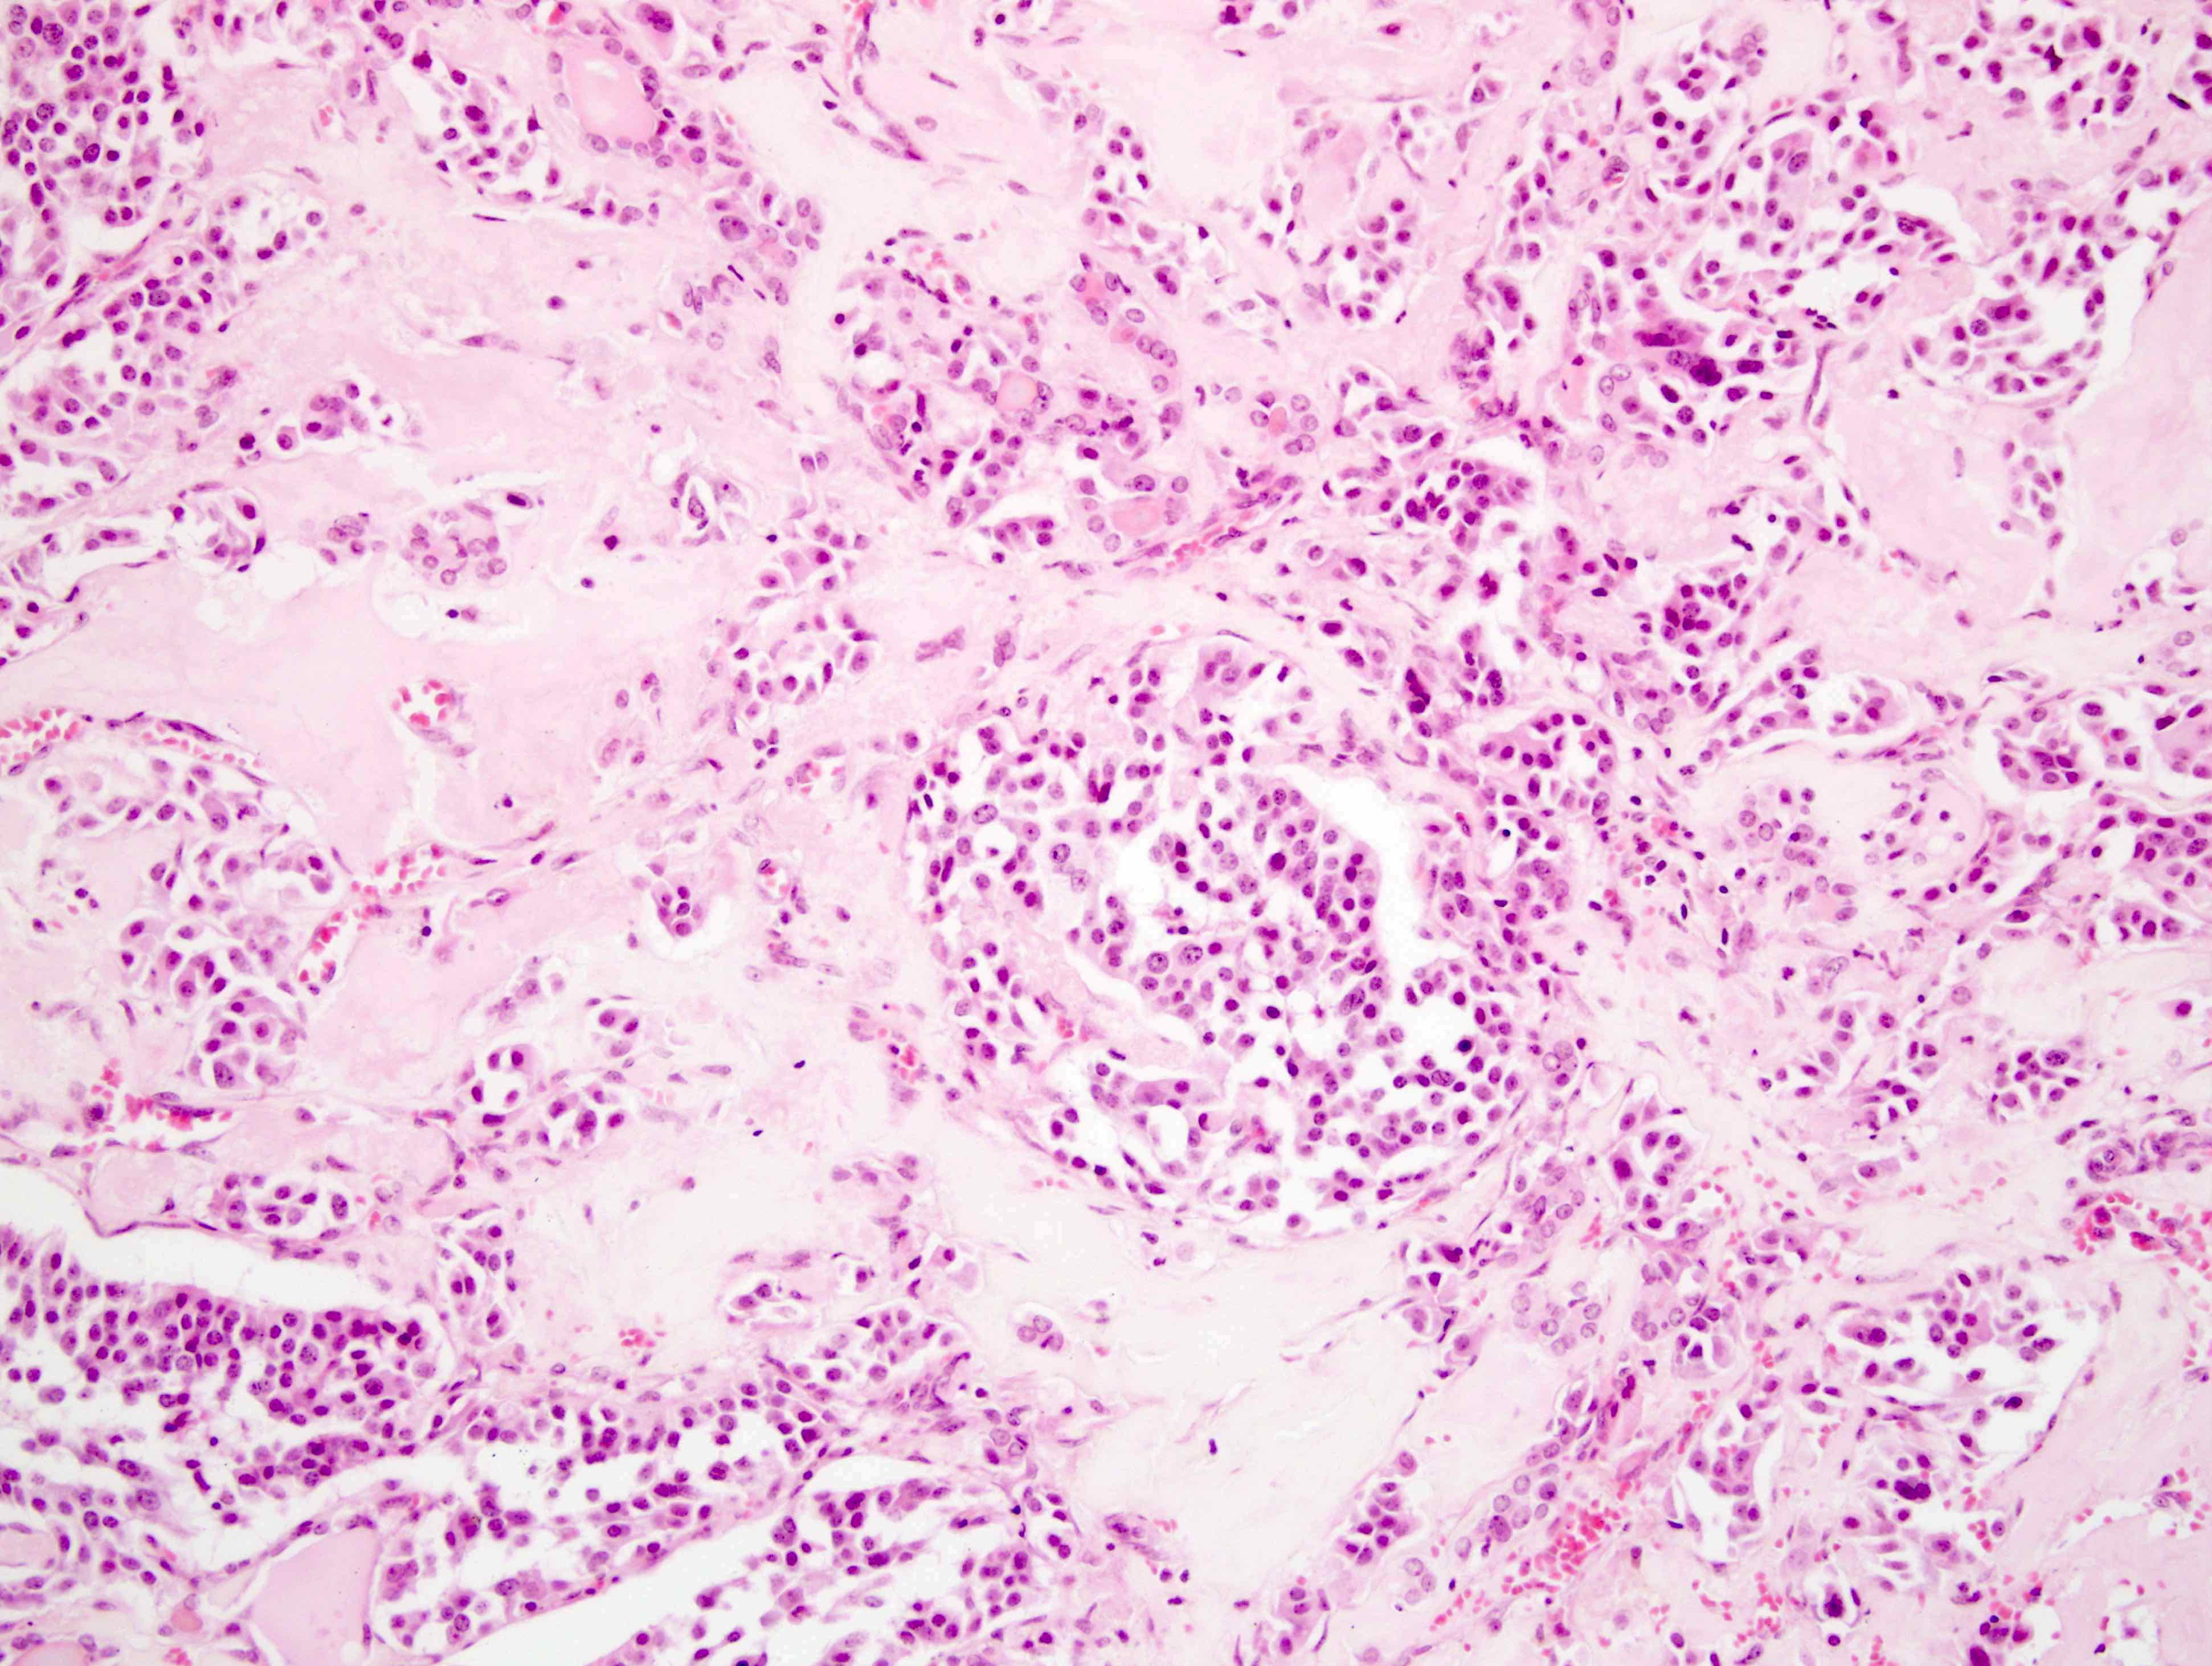

Microscopic (histologic) description

- Wide variety of morphology, can mimic any other thyroid malignancy

- Round, plasmacytoid, polygonal or spindle cells in nests, cords or follicles; often mixtures of these cells

- Round nuclei with finely stippled to coarsely clumped chromatin and indistinct nucleoli, occasional nuclear pseudoinclusion

- Eosinophilic to amphophilic granular cytoplasm due to secretory granules

- Generally low mitotic figures

- Stroma has amyloid deposits from calcitonin, prominent vascularity with glomeruloid configuration or long cords of vessels (Am J Surg Pathol 1995;19:642), coarse calcifications, occasional psammoma-like bodies

- Mucin in 42% (Arch Pathol Lab Med 1983;107:70)

- Often angiolymphatic invasion

- Occasionally marked neutrophilic infiltrate, oncocytic tumor cells, papillary patterns

- May entrap follicles

- C cell hyperplasia present in familial but not sporadic cases

Microscopic (histologic) images

Contributed by Shuanzeng Wei, M.D., Ph.D., Joseph Christopher Castillo, M.D. and Mark R. Wick, M.D.

AFIP images

Images hosted on other servers: